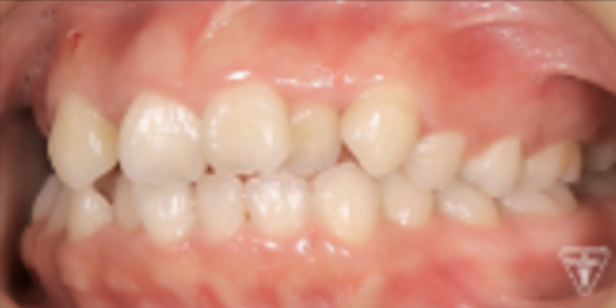

治療前